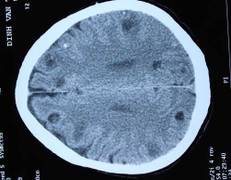

Bệnh viện Nhi Đồng 1, TP.HCM vừa tiếp nhận điều trị cho chàng trai 16 tuổi, ở tỉnh Kon Tum vì bị nhiễm sán heo ăn lên não, đã có biến chứng nặng gây động kinh.

Nhìn kết quả chụp CT sọ não các bác sĩ tá hóa khi thấy khoảng 50 ổ sán trong làm tổ trong não bệnh nhân.